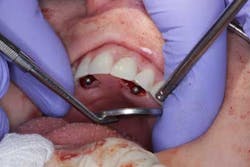

Surgery commenced. Implants on the lower arch were placed first (figures 7 and 8) and then we switched to the maxillary. The teeth were removed (figures 9 and 10) and the ridge was evened out (figures 11-13). The implants were aligned with the denture (figure 14) and then placed accordingly (figures 15-17). Healing caps were put on, and we were ready to start the restorative phase (figures 18-19).

The maxillary arch was indexed first as there was support from the palate to reference position (anterior/posterior) (figure 20). Then the lower was put into position to gain proper vertical dimension and occlusion. It, too, was then indexed; both upper and lower were given to the lab technician to start the conversion process. Next, impression copings were placed (one arch at a time) and secured with paperclips; a full-arch PVS impression was taken and likewise sent to the lab (figures 21-23). Finally, after the conversion process was completed, the bridges were secured in place on the multiunit abutments, torqued to 15nCm, and covered. Bite was adjusted and follow-up care was arranged (figures 24-26).